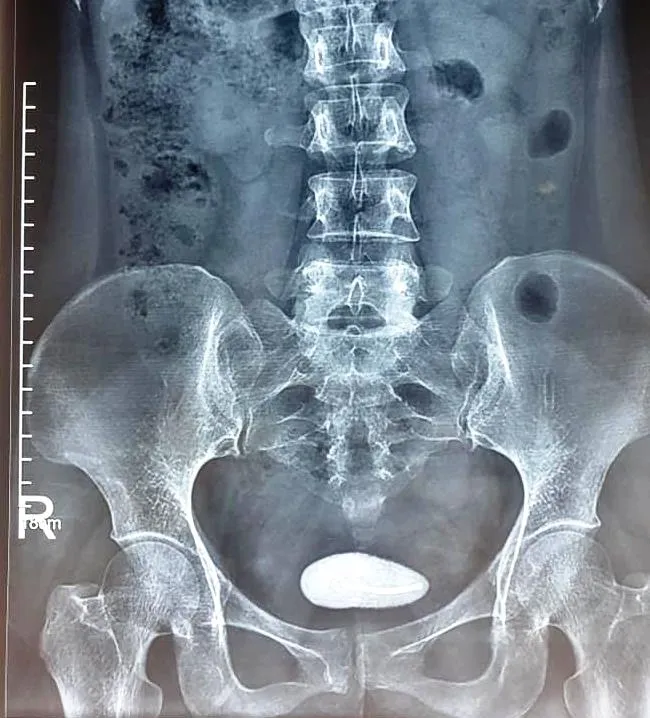

Hình ảnh chụp X.Quang cho thấy viên sỏi bàng quang bao quanh chiếc vòng tránh thai

Đây là trường hợp khá hiếm gặp khi bệnh nhân bị sỏi bàng quang do que tránh thai gây ra. Theo người nhà bệnh nhân, cách đây 4 năm, chị T. đã đặt vòng tránh thai, sau 20 ngày kiểm tra không thấy vòng trong buồng tử cung nghĩ rằng đã bị rơi ra ngoài nên cũng không đi kiểm tra lại. Gần đây, chị T. đau nhiều vùng hạ vị, tiểu buốt nên gia đình đã đưa đến Bệnh viện đa khoa tỉnh Tuyên Quang để khám bệnh. Sau khi thăm khám và làm các xét nghiệm, bác sĩ chẩn đoán bệnh nhân T. đã bị vòng tránh thai lạc vào bàng quang, dần dần hình thành sỏi bàng quang với kích thước (5x6)cm.